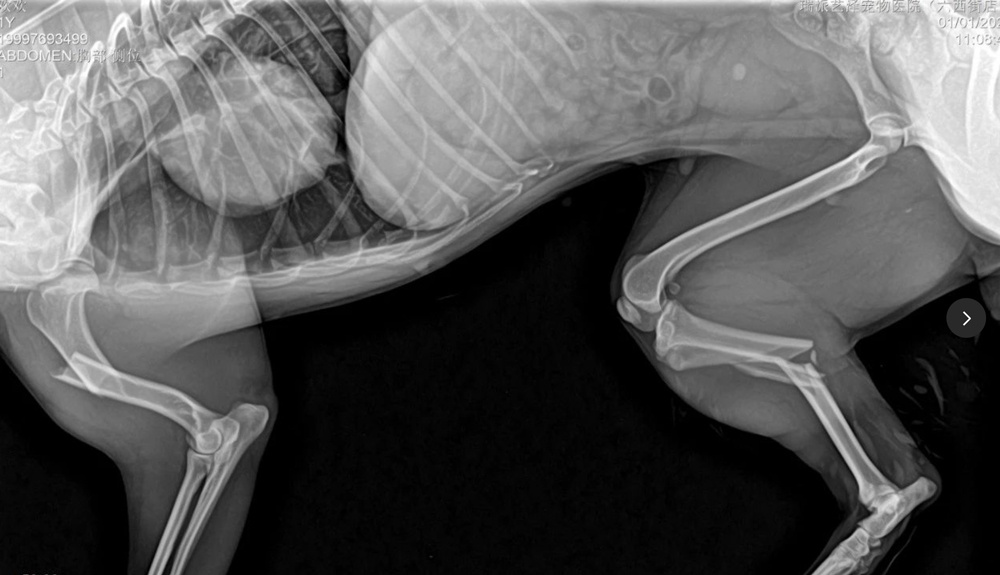

I have seen many cases of three leg fractures and two leg fractures in veterinary work. For cases of multiple limb fractures, it is very important to consider the stability of mechanical mechanics when planning surgery. Postoperative animals need to use this leg to carry weight while walking. If the mechanical stability is poor, postoperative weight-bearing can lead to implant fracture and fixation failure. Design a reasonable implant fixation scheme that ensures mechanical stability while also taking into account the biology of fractures, to ensure rapid healing before implant fatigue occurs. Adequate protection of soft tissue during surgery is crucial, and it is not enough to pursue stability of the implant while damaging too much soft tissue to affect healing.

After surgery, the legs were bandaged with "Lambert Jones bandages" for 5 days. After the swelling subsided, the bandages were no longer applied. After 10 days of care, the patient left the hospital and went home.